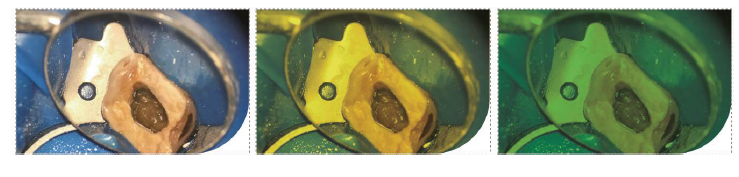

Sim. O modo fluorescência ajuda a identificar margens de cárie e preservar o máximo de estrutura sadia possível.

Ambos oferecem filtros laranja e verde; o G4 Pro adiciona modo fluorescência.